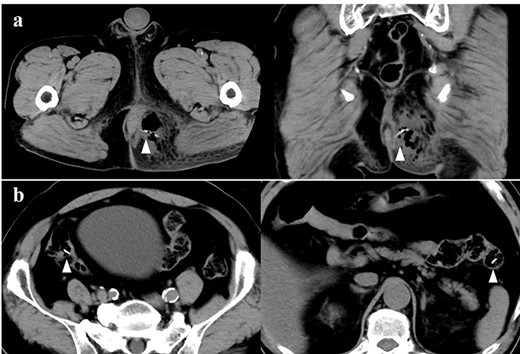

A 72-year-old man who had type 2 diabetes and was toothless visited our hospital because of anal pain that had started a week before. Swelling and redness were observed on his left-side buttock. Digital examination revealed swelling of the left-side anal canal. The blood examination test result showed elevated white blood cell count and C-reactive protein level. The computed tomography (CT) revealed a fluid cavity containing air in his left-side buttock and a high-density linear structure in the cavity (Fig. 1a). Furthermore, we found several linear structures in the gastrointestinal tract (Fig. 1b). We made a diagnosis of perianal abscess due to a foreign body and performed an emergency operation. We especially suspected a foreign body, particularly a fish bone, in the abscess cavity on the basis of the CT scan findings.

(a) A computed tomography scan showing the perianal abscess cavity containing air in the left-side buttock. The arrow indicates the fish bone in the abscess cavity. (b) Several high-intensity structures (white arrow) suspected as fish bone in the gastrointestinal tract.